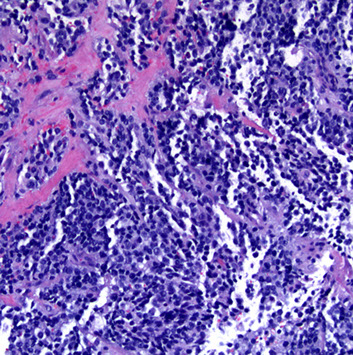

Myxoid Liposarcoma

2nd MCC liposarcoma; Low-grade c primitive non-lipogenic interstitial cells, signet ring lipoblasts, branching vascular, myxoid stroma

- 4th to 5th decade in lower extremities